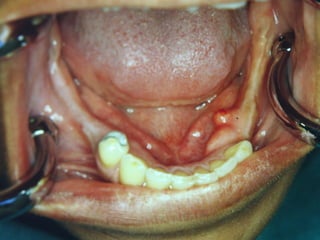

Grânulos de Fordyce

• Etiologia

• Características Clínicas

• Orientação Terapêutica